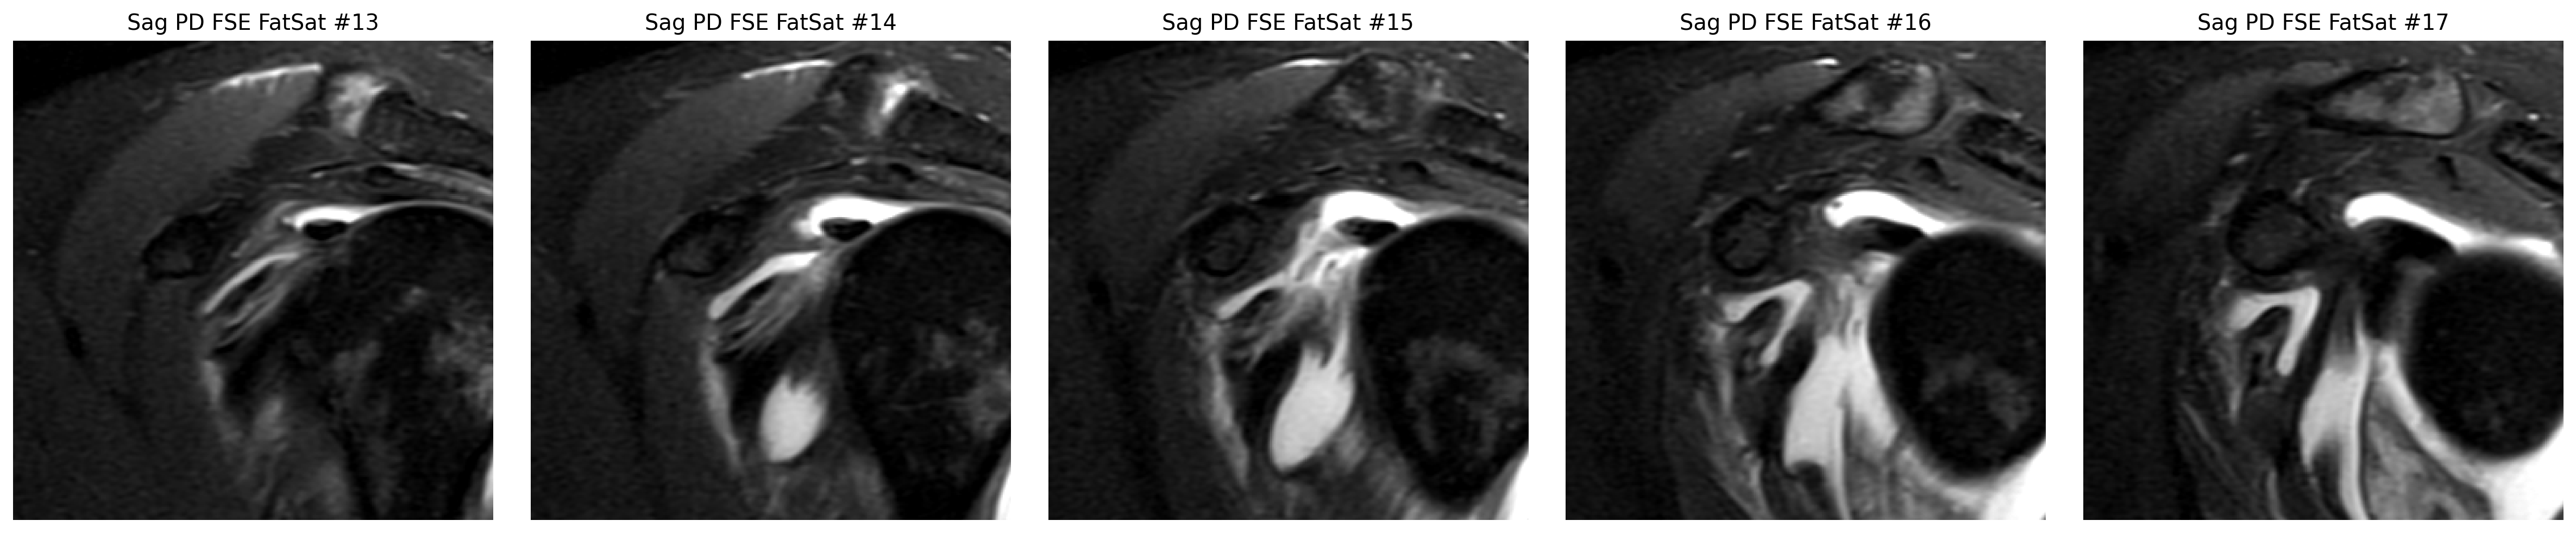

Focused coronal look at the supraspinatus footprint.

The cuff finding was checked in coronal and sagittal views, while the labrum was reviewed on axial arthrogram slices.